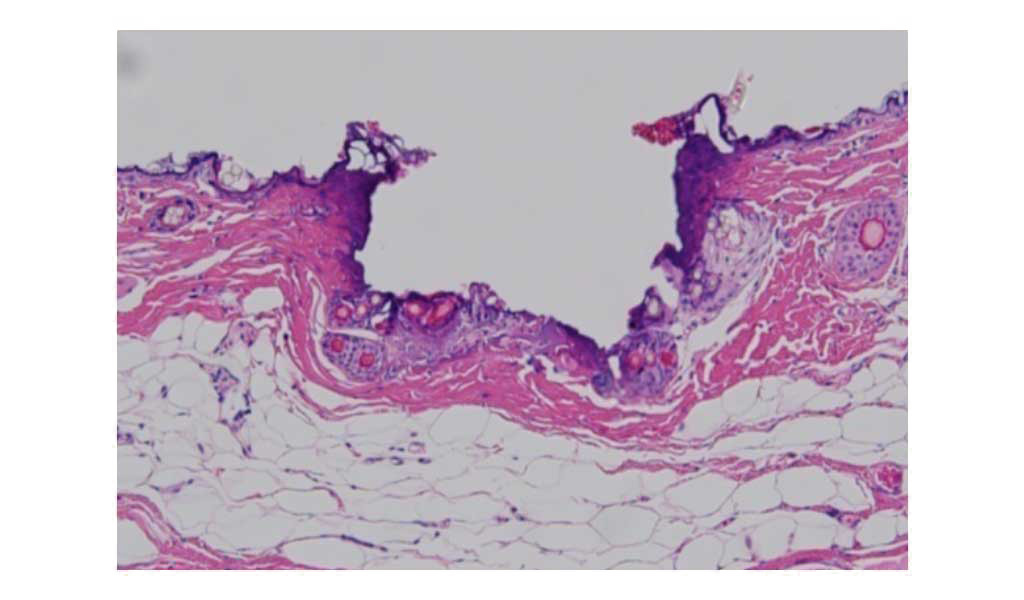

従来のレーザー治療がターゲット全面へ照射するのに対し、フラクショナルレーザーは点状にレーザービームを照射を行います。

フラクショナルレーザーは、CO2フラクショナルレーザーに比べ、凝固層がほとんどない治療(蒸散)が可能です。

ActionⅡ(AFL)

約0.3mmの微細な孔蒸散されている皮膚組織

MOSAIC(Non-AFL)

微細に凝固されてた皮膚組織